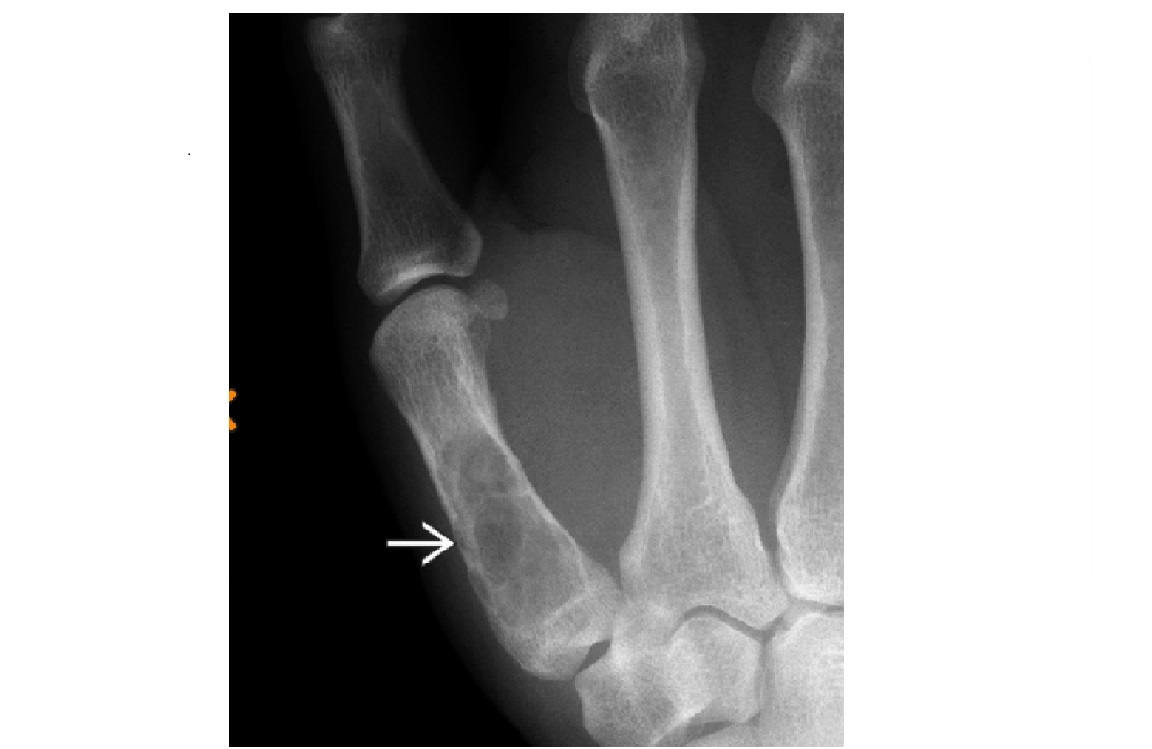

ENCHONDROMA

Commonest location Hands/feet

Long bones: proximal humerus > distal and proximal femur > proximal tibia

Intramedullary and metaphysis

multiple enchondroma

Maffuci - haemangioma

Olliers - multiple enchondroma only

DDx

-Brown tumor (hyperparathyroidism),

-sarcoid - lace like bone lesion phalanges

-intraosseous ganglion

-metastatic disease.